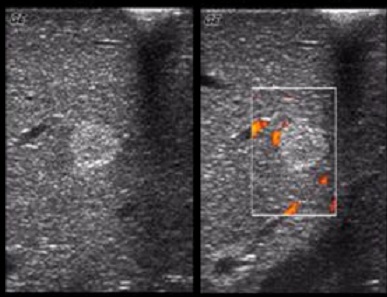

Image echographique de hemangiome : Aspect

echographique typique de hemangiome est lesion hyperechogene

homogene a contour net a renforcement d' echogen posterieure .

Absense de vascularisation au Doppler . Diminue de

l'echoriche a ísoechogenne en compresion ( manoeuvere de

compression )

Aspect echographique

typique d'une hemangiome : Image arrondie

hyperechogene , homogene a bord lisse uniquement au

lobe droit du foie |

Image echographique de

hemangiome du foie , sa bord est net , lisse et

hyperechoriche situe du foie droit |

Hemangiome du foie : Image de l'absence de vascularisation

de ce tumeur sur Doppler |